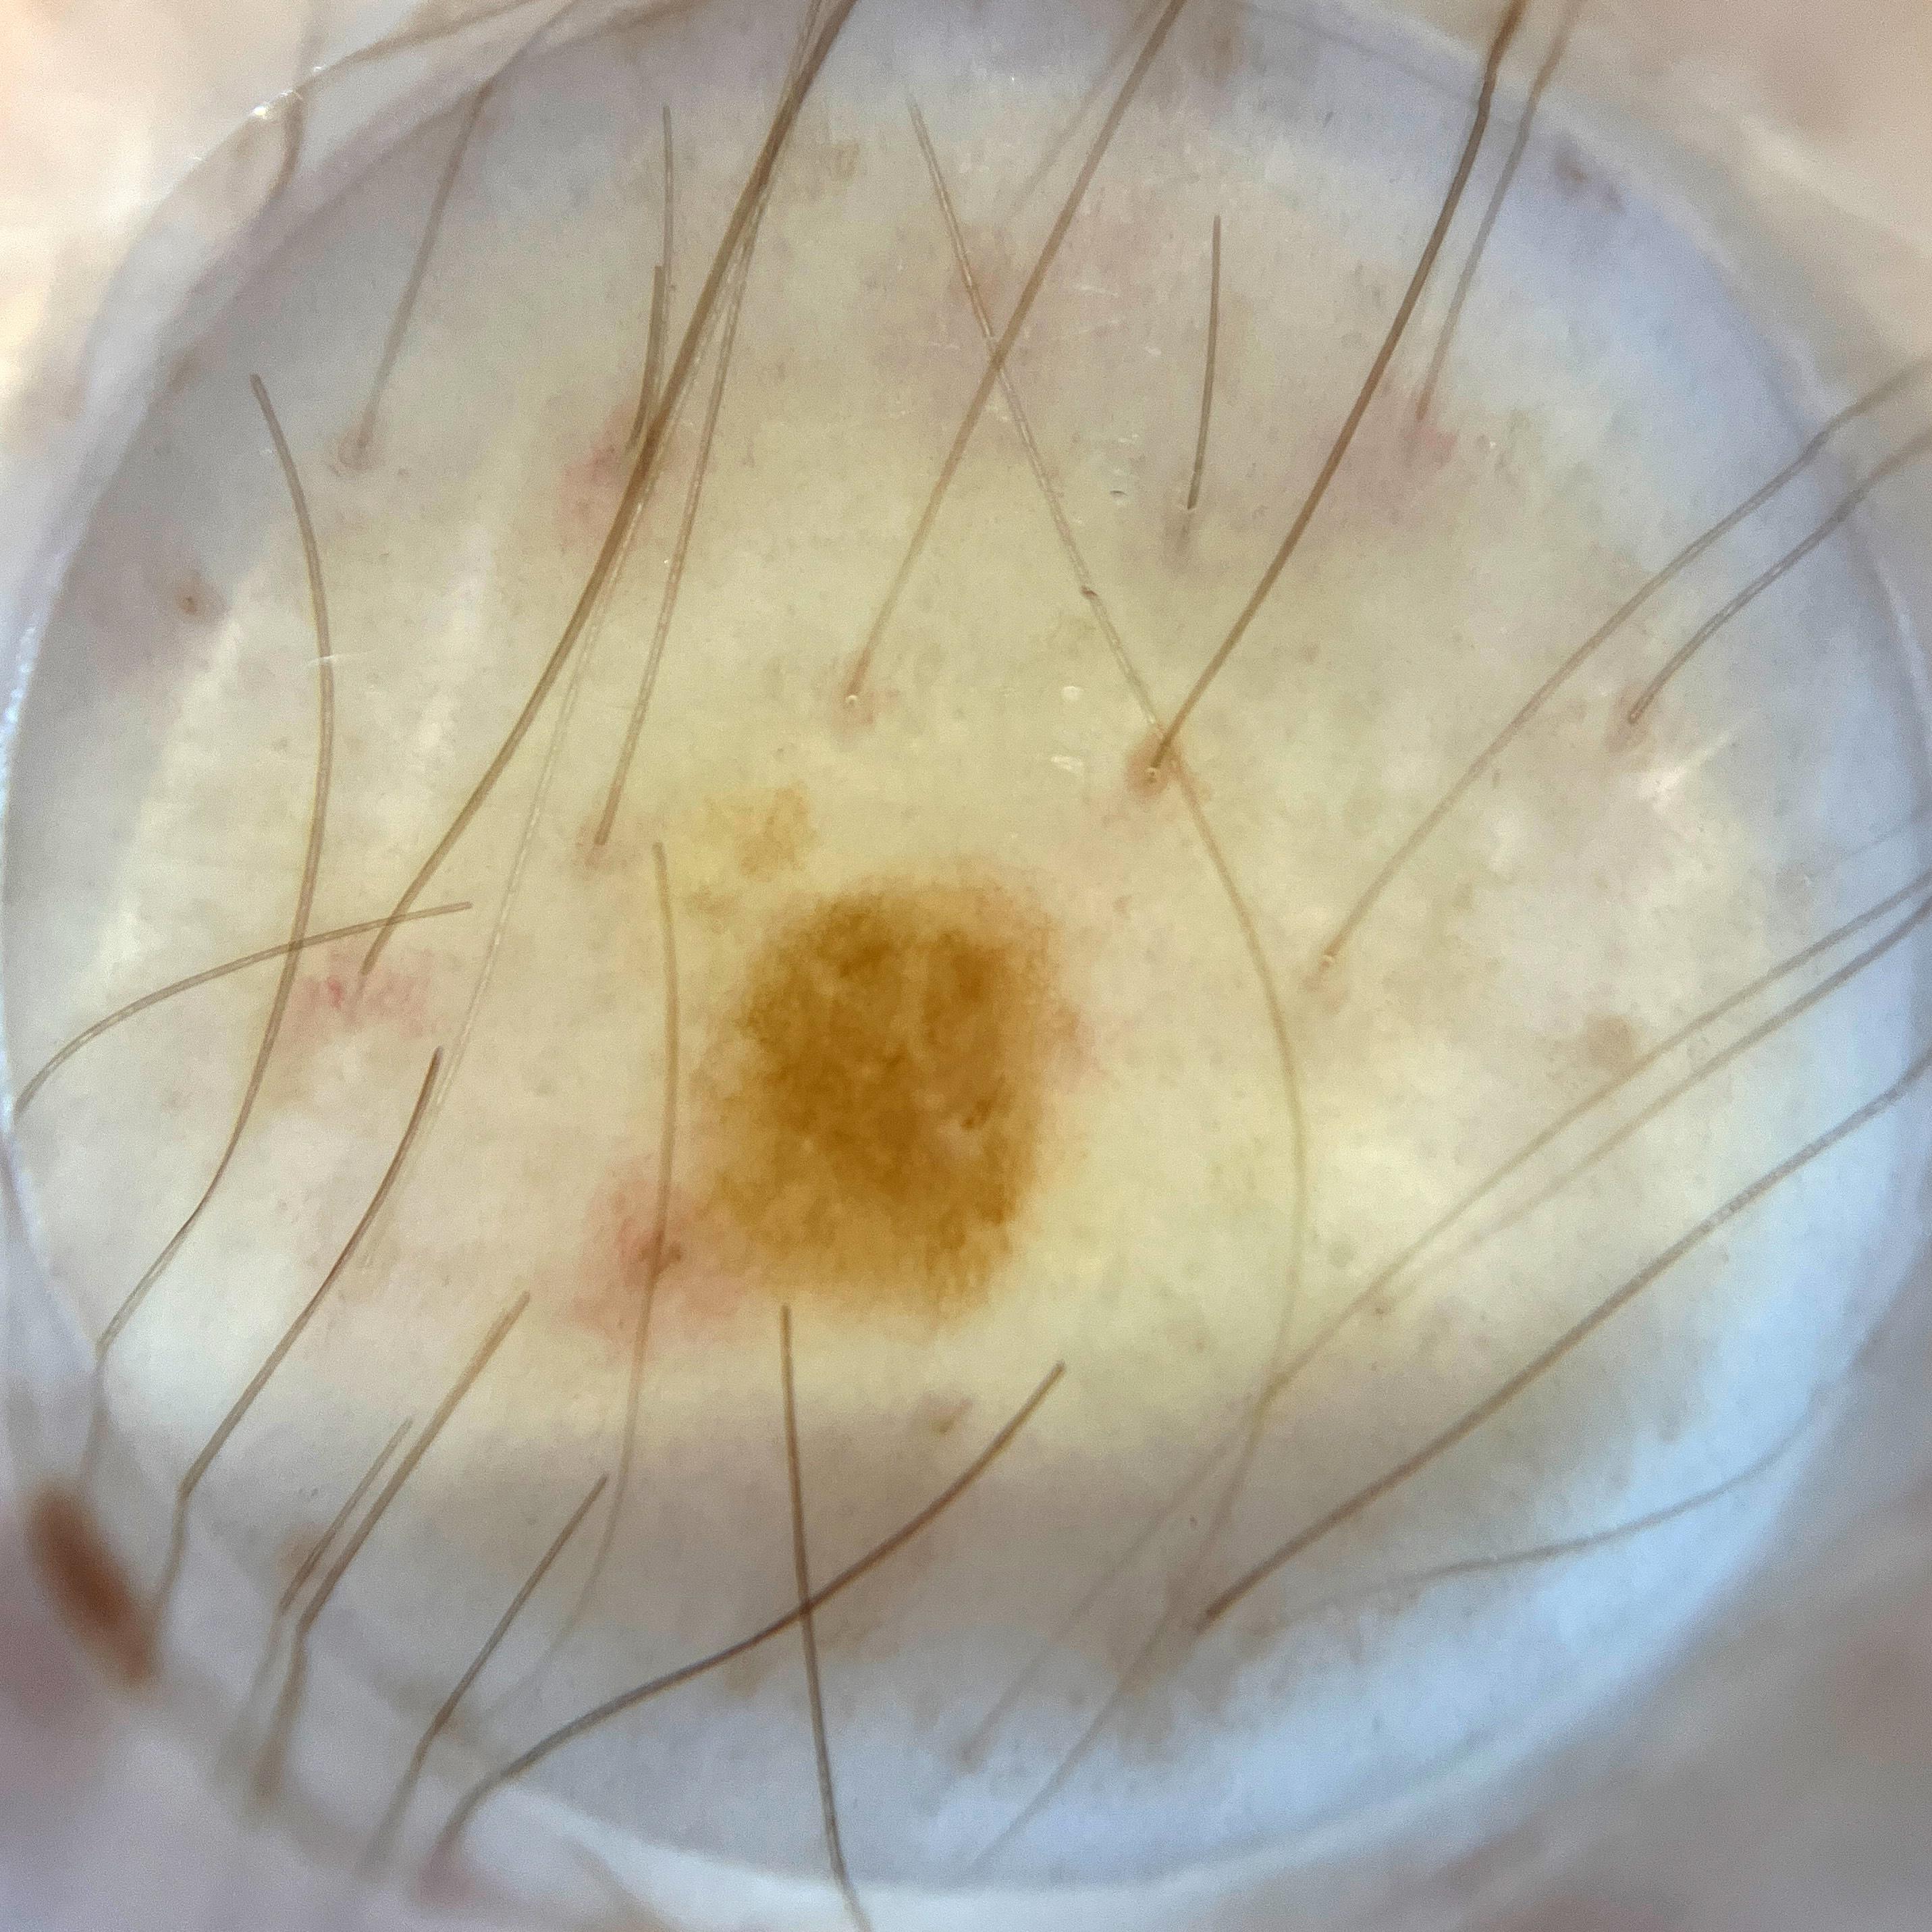

ISIC_8132457

IP_3351570

IL_0861336

acquisition_day 176

anatom_site_1 Lower extremity

anatom_site_general lower extremity

diagnosis_1 Benign

diagnosis_confirm_type single image expert consensus

image_type dermoscopic

lesion_id IL_0861336